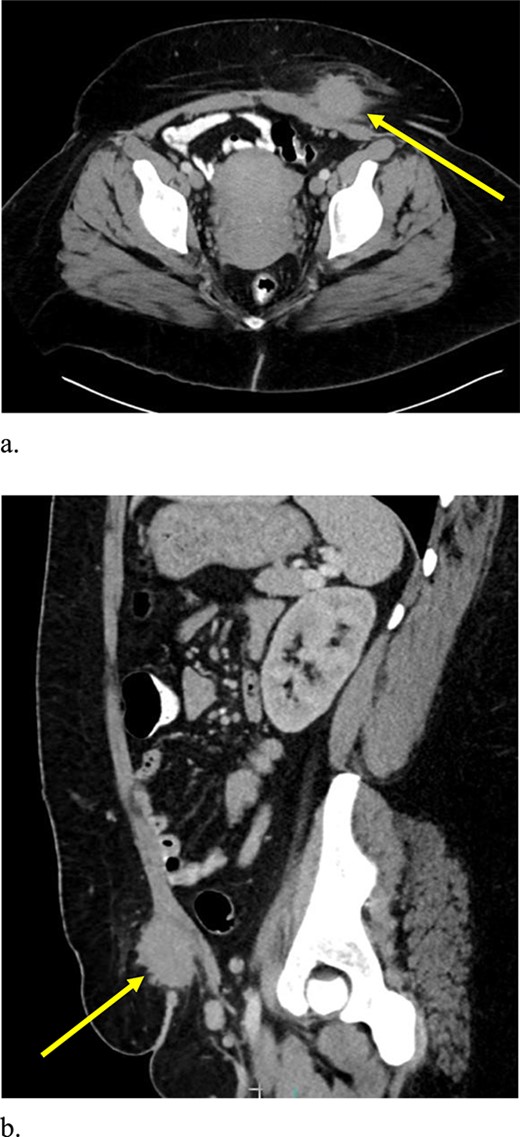

A 33-year-old female with past medical history of uterine fibroids and cervical insufficiency was initially seen with peri-incisional pain at the site of her Pfannenstiel scar since an emergency Cesarean section 16 months prior for eclampsia. She reported cyclical pain since that time, worse during menstruation and associated with swelling that resolved after menstruation. The discomfort and swelling persisted for 1 week after her last menstrual period, which prompted her to present for evaluation. On examination, a palpable, exquisitely tender mass was appreciated over the right side of her Pfannenstiel incision without evidence of discharge, erythema, or ulceration. Laboratory workup proved normal, and CT imaging revealed a soft tissue abscess-like collection anterior to the rectus abdominis muscle in the lower abdomen measuring 2.2 cm without intra-abdominal involvement (Fig. 9a and b). We deemed her a candidate for operative intervention given a high suspicion for endometrioma and her symptomatology.

Computed tomography axial (a) and sagittal (b) views of a 2.2 × 2.0 cm enhancing mass on the abdominal wall (arrows).